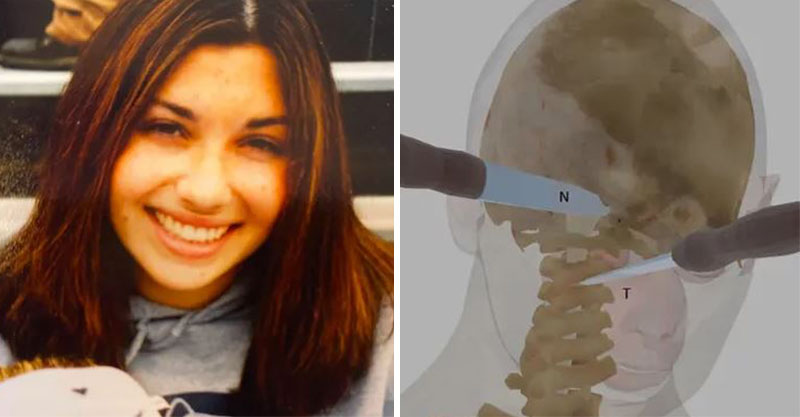

根據外媒《Fox News》的報導,2011年,美國費城一名27歲的女教師艾倫 (Ellen Greenberg) 被發現陳屍在公寓,她渾身是傷、身中20刀,有一半的刀傷都在後腦勺,甚至胸口還插著一把10英吋 (25.4公分) 的刀子。第一時間打電話報警的未婚夫山姆 (Sam Goldberg) 成了頭號嫌疑犯。

儘管現場血跡斑斑,艾倫的屍骨豊也有被移動過的痕跡,調查人員仍表示沒有在現場發現掙扎或打鬥證據,室內也沒有外力入侵的跡象,因此排除了謀杀殳的可能。起初,法醫根據艾倫的傷勢判定為他杀殳,但在警察部門介入商討後,死因竟改成了「自//殺」,山姆也因此全身而退。

這樣的結果讓艾倫的家屬完全無法接受,認為有10刀是刺進後腦怎麼可能是「自//殺」,甚至請了第三方驗屍專家鑑定,發現有2刀還是在心跳停止後刺入的。此外,山姆的供詞也起人疑竇,他聲稱自己是破壞門鎖才得以進屋,但犯罪現場的門鎖完好無缺。艾倫的爸媽決定訴諸媒體並向法院遞案,要求司法單位重啟調查女兒的案件。